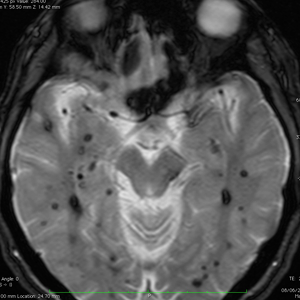

多発性海綿状血管腫 multiple cavernous hemangioma

家族性海綿状血管腫 familial cavernous hemangioma

この様な無数の海綿状血管腫を見ることがあります。多くの場合は家族性(遺伝性)の海綿状血管腫です。200個を超える海綿状血管腫があっても普通に何の障害もなく暮らしている患者さんもいます。脊髄の中にも発生しますから,脊髄のMRIもしていただきましょう。

小さな多発性の海綿状血管腫は,T2*(ティーツースター)という左の画像では見えるのですが,右にあるような普通のT1強調画像というのでははっきりみえません。